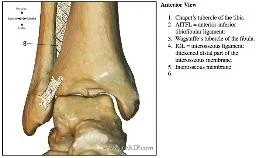

- Tibio-fibular Syndesmosis